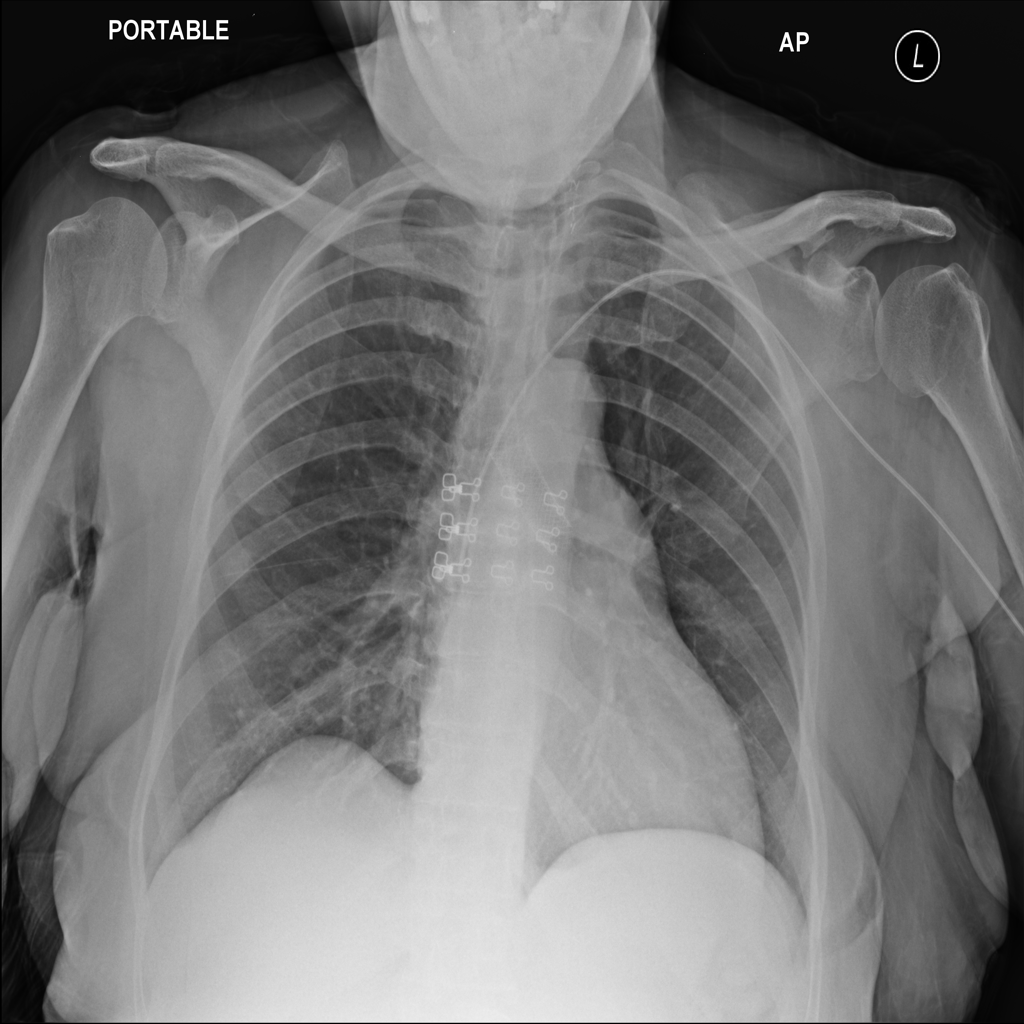

PAT-988D · IMG-001Nodule

PAT-988D · IMG-001

AP